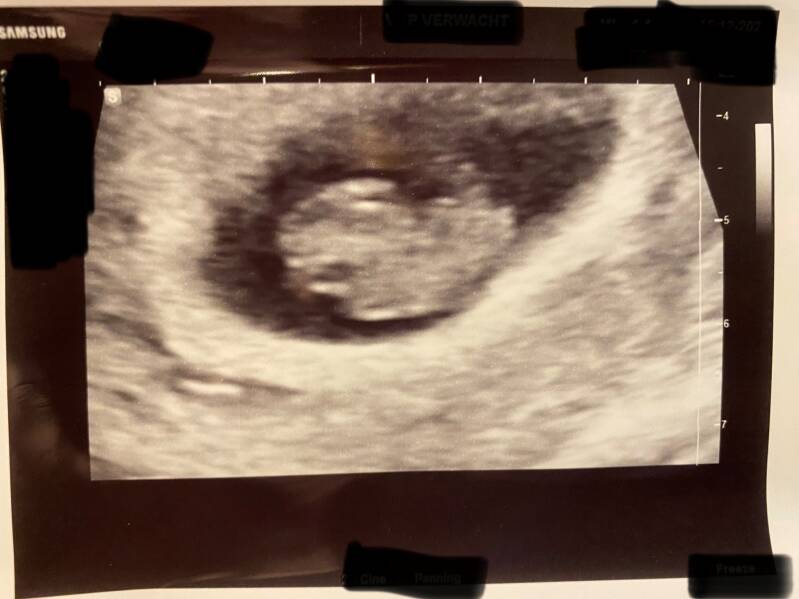

Wij hebben een topper van een verloskundige praktijk. Ze was meteen enthousiast, want ze weet hoe groot onze wens voor een derde kindje is. Ze zei ons meteen dat we het niet moesten afbreken, Met de studie van de 13weken echo komen er al heel veel afwijkingen aan het licht, dus dan zouden we met 13 weken altijd nog kunnen ingrijpen. Van alle kant groen licht dus. Ik mocht van haar met 6 weken zwangerschap langs komen om te kijken of er überhaupt een hartje klopte. En die klopt! Een wondertje dus! Mijn lichaam die zo snel alweer denkt een zwangerschap aan te kunnen, hoe dan? Ondertussen ben ik morgen (30-12-2022) al 11 weken zwanger. Morgen hebben we nog weer een echo. Ik vind elke echo nu wel wat spannender of het hartje nog klopt. Ik denk dat we morgen ook al echt een babytje gaan zien, zo zin in! Het is nog wel even spannend natuurlijk, eerst tot de 13 weken en later tot de 20 weken. Deze zwangerschap zit wel minder in mijn hoofd dan die van Jax en Ivy, maar misschien wordt dat na morgen wel anders als we iets meer handjes en voetjes gaan zien op het scherm๐ฅฐ.